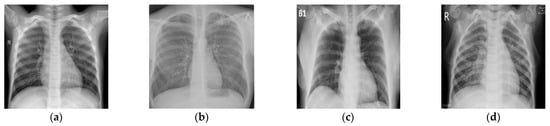

In Figure 2, we provide some representative examples of the 4 classes.

The Samples of X-rays from 4 classes: (a) Normal sample; (b) Tuberculosis sample; (c) Coronavirus sample; (d) Viral-Pneumonia sample.